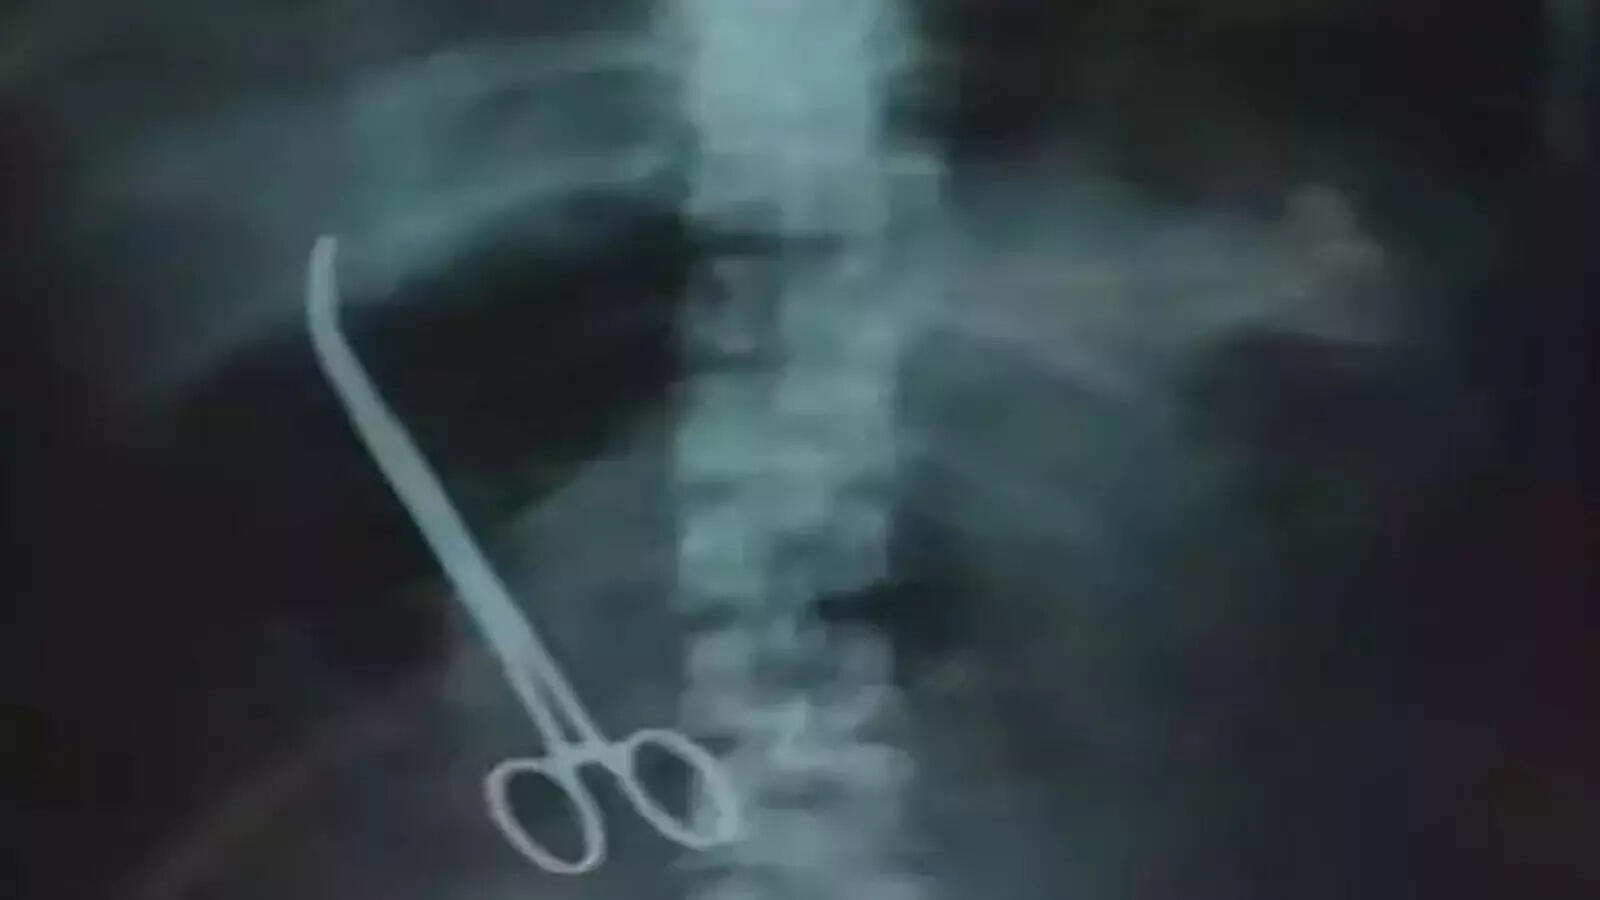

महिला, जिसका नाम गोपनीय रखा गया है, को एक नियमित ऑपरेशन से गुजरना पड़ा था। सर्जरी सफल मानी गई और उसे कुछ दिनों के बाद अस्पताल से छुट्टी भी मिल गई। हालांकि, कुछ समय बाद उसे पेट में असहनीय दर्द और अन्य समस्याओं का अनुभव होने लगा। लगातार बिगड़ती स्वास्थ्य स्थिति को देखते हुए, जब दोबारा जांच की गई, तो डॉक्टरों के होश उड़ गए। एक्स-रे और अन्य इमेजिंग तकनीकों से पता चला कि महिला के पेट के अंदर एक धातु का उपकरण मौजूद था।

यह कोई छोटा-मोटा औजार नहीं था, बल्कि एक फोरसेप्स था, जो सामान्यतः सर्जरी के दौरान उपयोग किया जाता है। इस खोज ने सभी को हैरान कर दिया। सवाल यह उठा कि इतनी महत्वपूर्ण और गंभीर भूल कैसे हुई? चिकित्सा समुदाय में इस घटना ने लापरवाही और सुरक्षा प्रोटोकॉल की कमी को उजागर किया। इस तरह की घटनाएं मरीजों के विश्वास को भी गहरा आघात पहुंचाती हैं।

जब महिला के पेट में फोरसेप्स की मौजूदगी की पुष्टि हुई, तो संबंधित चिकित्सा दल और अस्पताल प्रबंधन के लिए यह एक गंभीर चिंता का विषय बन गया। प्रारंभिक जांचों के बाद, डॉक्टरों ने स्थिति का आकलन किया और यह निष्कर्ष निकाला कि हालांकि फोरसेप्स का पेट में रहना एक अत्यधिक गंभीर और असामान्य स्थिति है, लेकिन वर्तमान में इससे महिला के स्वास्थ्य को कोई तत्काल खतरा नहीं है। यह बयान कई लोगों के लिए विरोधाभासी लग सकता है, लेकिन डॉक्टरों ने इसके पीछे के तर्क को स्पष्ट किया।

उनका मानना था कि फोरसेप्स एक ऐसी जगह पर स्थित था, जहां से वह किसी भी महत्वपूर्ण अंग को नुकसान नहीं पहुंचा रहा था। यह एक धातु का उपकरण था और शरीर के अन्य ऊतकों के साथ इसके संपर्क से कोई संक्रमण या अन्य प्रतिक्रिया देखने को नहीं मिल रही थी। डॉक्टरों ने यह भी स्पष्ट किया कि फोरसेप्स के चारों ओर शरीर ने एक प्रकार की सुरक्षा परत बना ली थी, जिससे वह अपने स्थान पर स्थिर हो गया था।